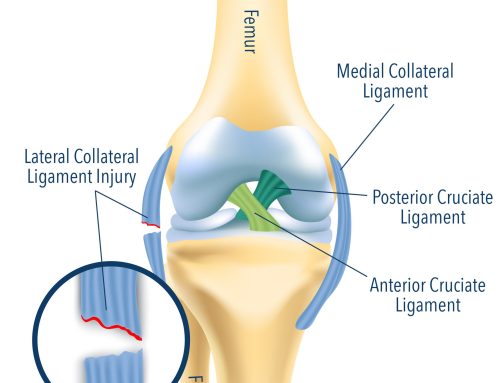

Adhezinio kapsulito priežastis gali būti trauminė (pvz. lūžis, išnirimas ar minkštųjų audinių pažeidimas) arba netrauminė (pvz. osteoartritas, rotatorių manžetės tendinopatija ir kalcifikuotas tendinitas). Taip pat šis pažeidimas gali būti susijęs su kita sistemine liga, pvz. skydliaukės, antinkščių, plaučių veiklos sutrikimais, hiperlipidemija (Dias R, Cutts S, Massoud S, 2005; Robinson CM et al., 2012).